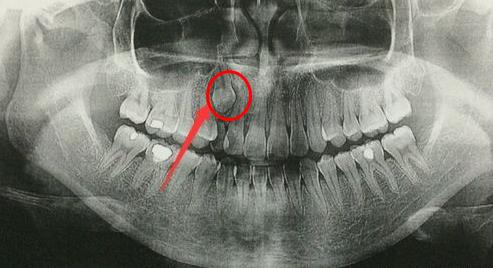

埋伏牙是什麽(me) ?顧名思義(yi) ,就是因為(wei) 各種原因完全埋伏在牙槽骨,沒有露頭的那一類牙齒,肉眼是看不到的,需要拍片才能察覺出它的存在。那麽(me) 這種牙齒還能自己長出來嗎,要怎麽(me) 辦呢?

埋伏牙